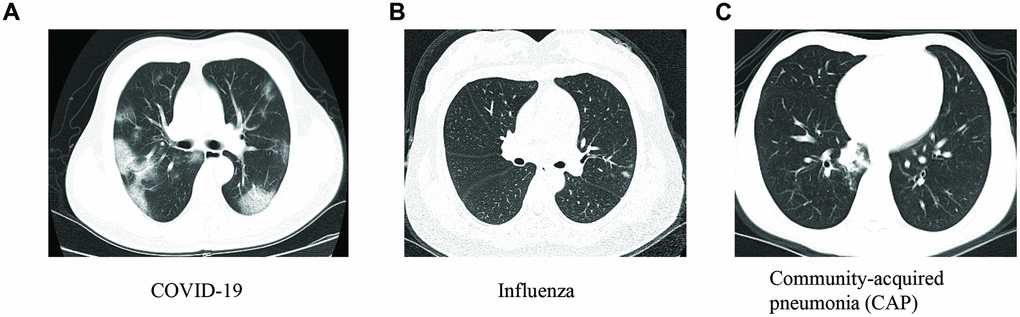

This study was conducted in a region outside of Wuhan, the epicenter of the COVID-19 outbreak. Out of 50 suspected patients enrolled in the discovery and internal validation cohorts, 8 had COVID-19, 8 had seasonal flu (influenza), and 34 had community-acquired pneumonia (CAP) (Table 1). There were no significant differences in characteristics among the three groups, including age, sex, clinical symptoms, WBC, and LYC. Compared to those with influenza and CAP, patients with COVID-19 had significantly lower LYP values (P < 0.001). Representative chest CT images for COVID-19, influenza, and CAP are shown in Figure 1. The external validation cohort from another hospital included 11 COVID-19 patients, 20 with influenza, and 24 with CAP (Table 2).

The CT examination was performed with a multislice spiral CT machine (TOSHIBA Aquilion 16, Japan) by two senior chest diagnostic radiologists who used a PACS workstation to read the axial images of standard 5 mm slice thickness, and 1 mm slice thickness images were used for multislice reconstruction to observe the lesions. The typical imaging manifestations of the patients were ground-glass opacification, consolidation, reticular shadow, and air bronchial sign, and most of the lesions were distributed in the subpleural areas. CT scans were read independently by two radiologists (blinded for review). Disagreements were resolved by a third experienced thoracic radiologist.